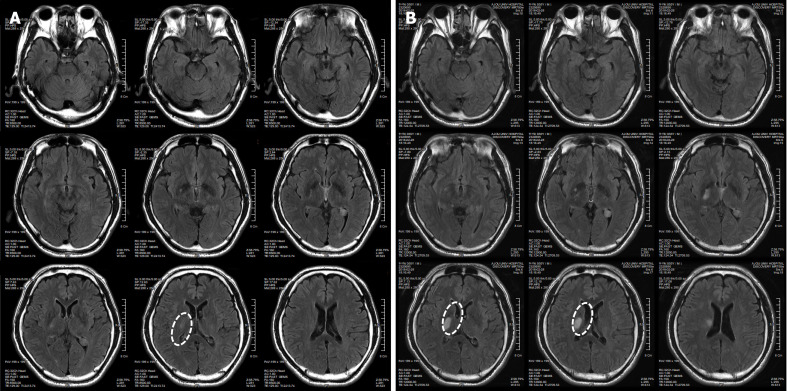

患者于2018年2月17日至18日出現(xiàn)暫時(shí)性無力癥狀,早上醒來后突發(fā)急性中風(fēng),導(dǎo)致左上肢和下肢癱瘓?;颊咴诖髮W(xué)醫(yī)院急診室被診斷為Rt紋狀體囊性梗死(圖1A)。他于2018年3月2日出院,僅接受了阿司匹林處方,因?yàn)楦鶕?jù)腦計(jì)算機(jī)斷層掃描 (CT) 掃描,他的腦血管正常,盡管他的病情在住院期間惡化(圖1)。出院當(dāng)天,他被送往康復(fù)??漆t(yī)院接受長期康復(fù)治療。然后他于2018年3月13日來韓國首爾生物美容與健康公司 (bBHC)-干細(xì)胞治療與研究所 (STRI)接受干細(xì)胞治療。

圖1:微創(chuàng)人臍帶間充質(zhì)干細(xì)胞移植前患者的腦部計(jì)算機(jī)斷層掃描圖像。